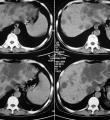

(7)CT显示双肾增大,外形呈分叶状,有多数充满液体的薄壁囊肿。